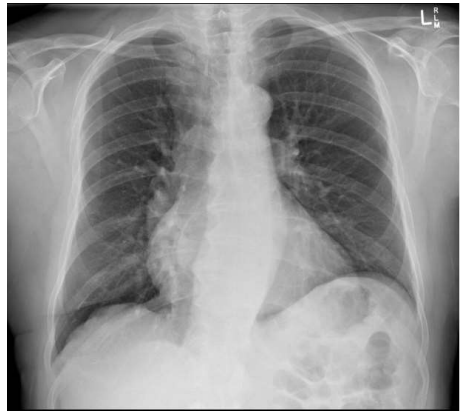

Qual das seguintes patologias abaixo estaria mais relacionada aos achados da seguinte radiografia de tórax?

Insuficiência aórtica

Coarctação da aorta

Embolia pulmonar

Estenose mitral

Tamponamento cardíaco